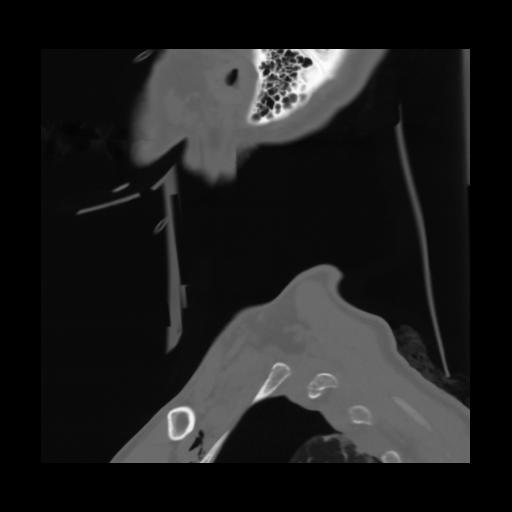

14 P.BLANDAS,,Sagittal,2.000,P.BLANDAS,Sagittal,